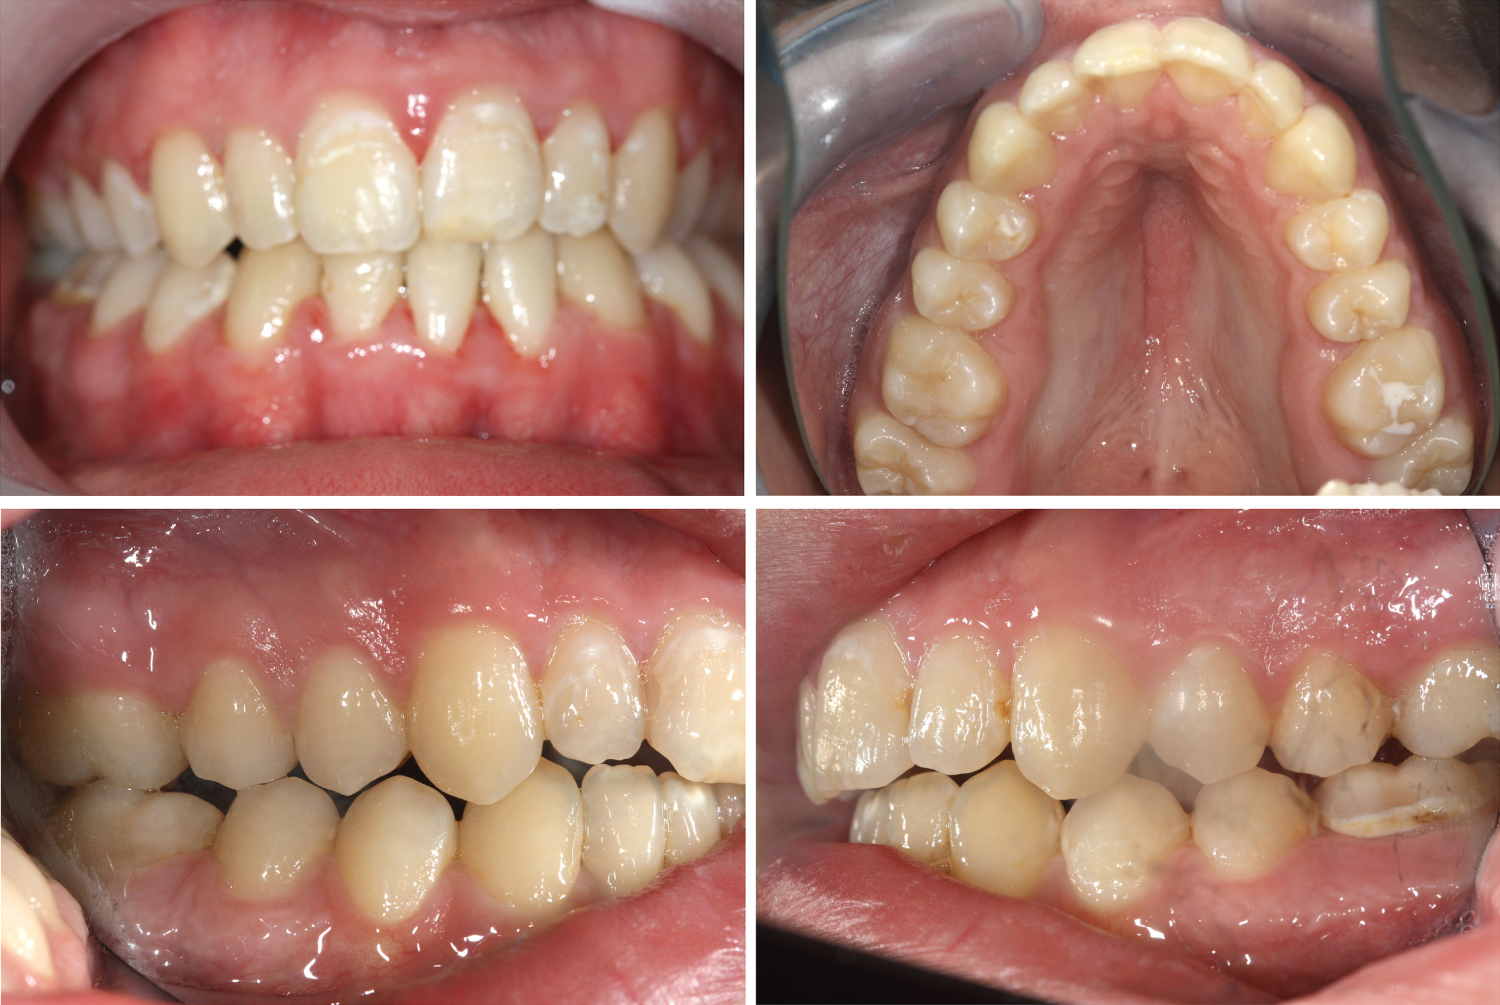

Figure 5: Frontal view after debonding (above left), maxilla expansion and space closing after loss first molars (above right), right and left occlusion are not ideal because of extraction of one lower incisor (below). View Figure 5

1.5 years after start of treatment all remaining 25 teeth were in occlusion (Figure 3). The appliance was removed six months later. Because of asymmetric extraction there was no alignment of the mid lines and no full interdigitation of all teeth. The patient confirmed improvement of masticatory function, mouth closure and permanent nose breathing. We recommended hard food and long-lasting mastication for strengthening of masticatory muscles (Figure 5).

The extraoral clinical examination revealed a concave profile and long face with higher lower part (Figure 1). The oral examination showed an open bite of 5.0 millimeters with a slope of the maxillary occlusal plane to the left. Only four teeth were in occlusion on the right side. Maxilla and mandible were constricted with severe crowding in the frontal region. First molars at both sides in the maxilla had been extracted years before due to caries (Figure 2). The OPT showed all third molar germs and normal root lengths (Figure 2). The cephalogram reflected the skeletal open bite with a high ML/NL angle of 38.9 degrees. The ANB angle of 6.6 degrees signalized a Class II relationship. The proportion between the middle and the lower face underlined the dolichocephaly structure with 55.0 to 82.4 millimeters (Figure 3). Oral hygiene was poor.